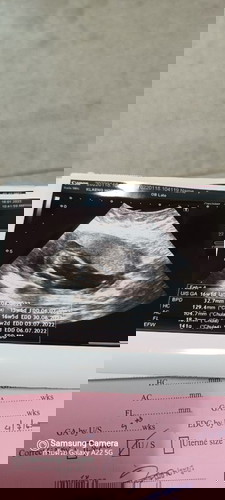

ที่เห็นชัดๆใช่ส่วนขาน้องรึเปล่าคะมีใครรู้มั้ยคะว่าน้องเป็น ช.รึ ญ. #ขอบคุณสำหรับคำตอบค่ะ